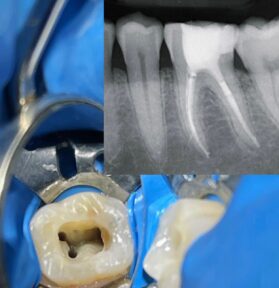

Treatment Gallery

Every smile tells a unique story. Discover the incredible transformations we have achieved for our patients through professional photographic documentation that captures every detail.

We believe the best dentistry mimics nature. Our practice is based on restoring your teeth while respecting their original structure as much as possible, using minimally invasive treatments that are as durable and functional as they are beautiful.

Comprehensive restorations that return function, aesthetics, and confidence, completely respecting your natural biology.

With over 25 years of clinical practice, I have worked on diverse, complex cases requiring a multidisciplinary approach. My experience has allowed me to develop skills and techniques that enable me to offer high-quality, personalized treatments to my patients.